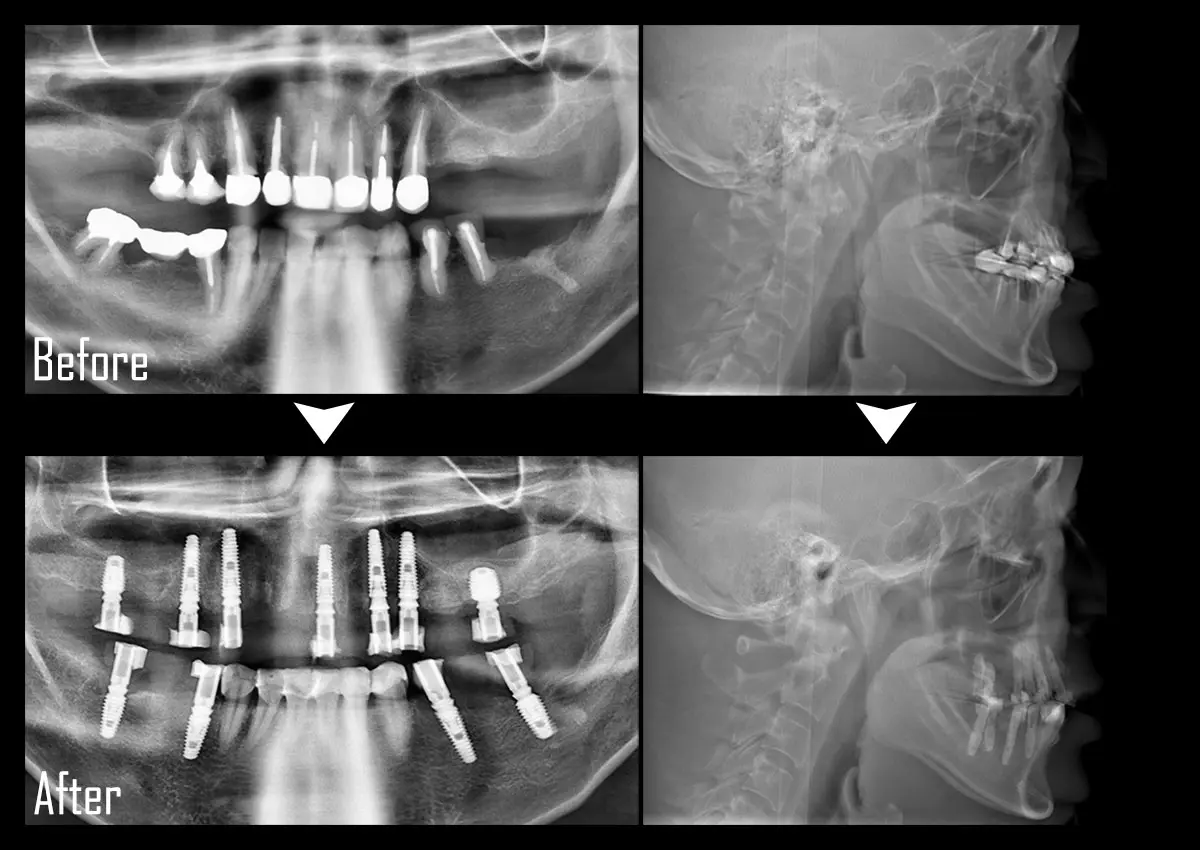

CASE:All-on-4(オール・オン・フォー)

症例All-on-4(オール・オン・フォー)

主訴 奥歯がない

治療内容 上下合計11本のインプラント治療を行い、全顎治療を実施

標準費用(自費) 781万円